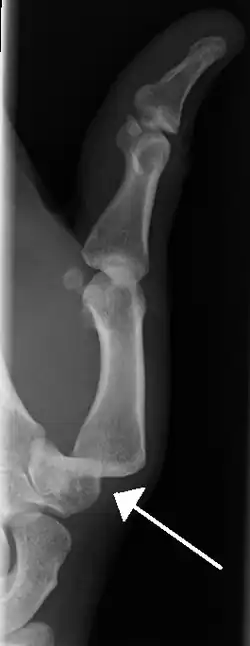

Radiograph of left index finger dislocation